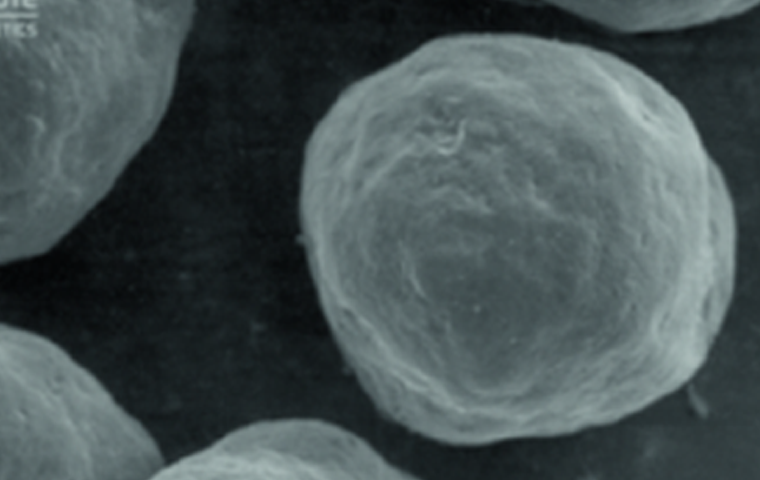

겔 캐리어 내 CaHA입자

수용성 겔 캐리어와 미세한

CaHA(칼슘 하이드록시아파타이트) 입자로

구성된 칼슘 미네랄 필러입니다.